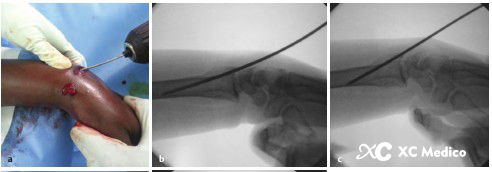

Во -первых, выполняется закрытое восстановление перелома, с медленной и непрерывной тягой, а дорсальное и радиальное смещение корректируется с помощью сгибания пальма и локтевого отклонения. После сокращения рука помещается на свернутый лист, поддерживая пальмовое сгибание и локтевое отклонение (рис. 2а, б) и фиксируется не менее трех чрескожных проводов Киршнера.

Первый K-провод вводится в бугорку Листера, наклонен при 45 ° и направлена на пальмовую кору проксимального фрагмента кости на длинной оси радиуса. Если точка вставки находится на локтевой стороне бугорки Листера, сухожилие Extensor Ollicis может быть повреждено.

Вторая K-провода вставлена 0,5 см дистальна к радиальному стилоидному процессу, K-провода находится под углом 60 ° к радиальной оси и проникает в локтевую кору, проксимальную к перелому.

Третий K-провода фиксируется к фрагменту Lunate Fossa Bone 0,5 см дистально до линии сустава запястья, расположенной между четвертым и пятым компартментами разгибателей. K-провода прикреплена к ладонильной стороне радиуса под углом 45 °, как показано на рисунках A и B ниже.

Классическая чрескожная фиксация проволоки Киршнера расстановки дистального радиуса показана на рисунках AE ниже.